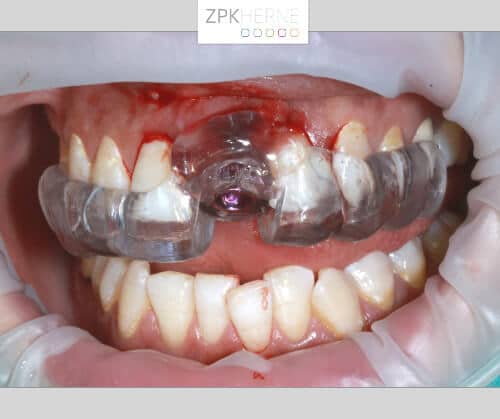

2. Im nächsten Schritt wird die Bohrschablone anprobiert und die Bohrung Schritt für Schritt durchgeführt. Das Implantat wird maschinell eingebracht und radiologisch kontrolliert.

Kieferansicht mit befestigter Bohrschablone im Oberkiefer